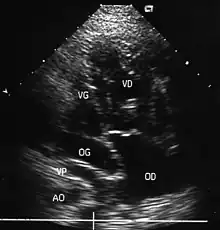

- le signe d'appel habituel est la perte du croisement des gros vaisseaux. Normalement, l'aorte et le tronc pulmonaire se croisent peu après leur sortie du cœur. Il est donc impossible de dérouler les deux vaisseaux sur un même plan de coupe. Quand l'aorte est vue longitudinalement, le tronc pulmonaire n'apparaît qu'en section transversale ("aorte en long, tronc pulmonaire en rond") et vice-versa. Dans la D-TGV simple, la plus fréquente, les vaisseaux ont un trajet parallèle et peuvent donc être visualisés longitudinalement simultanément.

- la confirmation est obtenue par l'analyse des gros vaisseaux et de leurs connexions aux ventricules. L'aorte est caractérisée par le fait qu'elle décrit une crosse, donne naissance aux vaisseaux à destinée céphalique et est le vaisseau qui monte le plus haut dans le thorax. Le tronc pulmonaire est caractérisé par sa bifurcation précoce en deux branches, les artères pulmonaires droite et gauche. Sur un cœur par ailleurs normal, le ventricule droit est situé en avant et à droite du ventricule gauche, le tronc pulmonaire est donc le vaisseau le plus antérieur. La TGV se caractérise par la position antérieure du vaisseau qui décrit la crosse et donne les vaisseaux céphaliques : l'aorte.